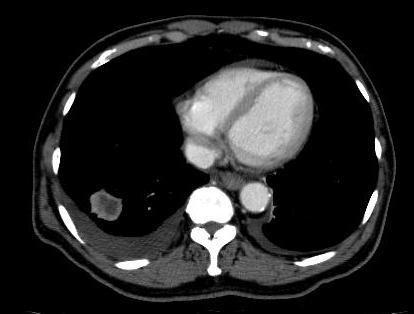

CT Chest/ Abdomen / Pelvis

Lung / bowel / renal primary

Lung metastasis

Lung cancer Renal cell cancer